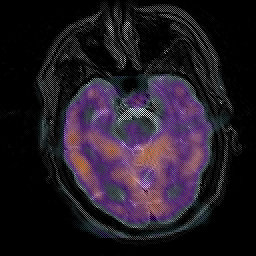

Subacute Stroke, overlay -- Slice #8

[Home][Help][Clinical] Slice 8